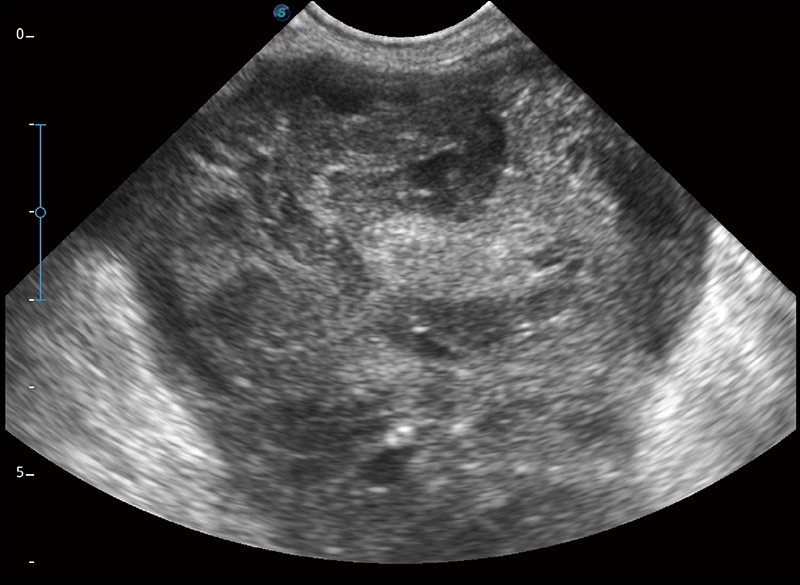

α1卓越的图像质量和便捷的工作流程,使每位宠物医生都能轻松扫查。其全面的兽用应用功能和紧凑型的结构设计,可以满足动物检查的多种需要。专业的预设检查模式和多领域测量软件包有助于为不同类型的动物提供检查, 让宠物医生能够出色的完成工作。

在不牺牲时间分辨率的情况下提供出色的图像

空间复合成像

优化不同角度的图像